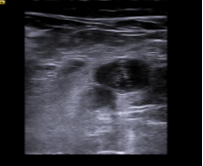

Hallazgos ecográficos

Ecografía clínica en el mismo momento de la consulta: vena poplítea derecha y vena safena derecha no compresibles imagen hipoecocicas sugestivas de tombo sugiere trombosis venosa profunda en territorio poplíteo. Se deriva a hospital.

Ecografía diagnóstica Doppler de confirmación en hospital: trombosis venosa profunda poplítea derecha.